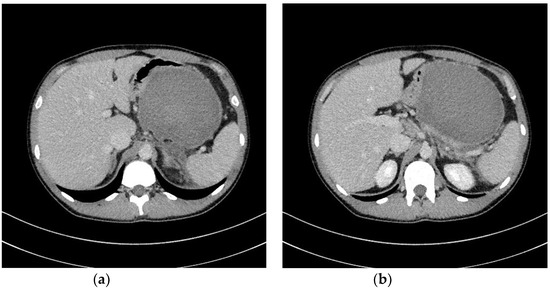

| Transmural endoscopic drainage with use of plastic stents | Active (with nasal drain) or passive (without nasal drain) transmural drainage enabled via insertion of plastic stent or stents through the transmural fistula into lumen of necrotic cavity. Mostly used in cases of well-liquefied collections of WOPN with small number of necrotic tissues in the lumen of WOPN, which usually take place after six weeks from the beginning of ANP. This type of drainage should be used in cases, where there is no necessity to perform endoscopic necrosectomy. |

| Transmural endoscopic drainage with use of SEMSs | Active (with nasal drain) or passive (without nasal drain) transmural drainage accomplished via insertion of metal stent (SEMS) through the transmural fistula into lumen of necrotic collection. Indications for this type of drainage are extensive WOPN containing poorly-liquefied necrotic tissues, in which endoscopic necrosectomy may be necessary in the next step. SEMSs are usually used in the endoscopic treatment of WOPN up to sixth week from the beginning of ANP. |